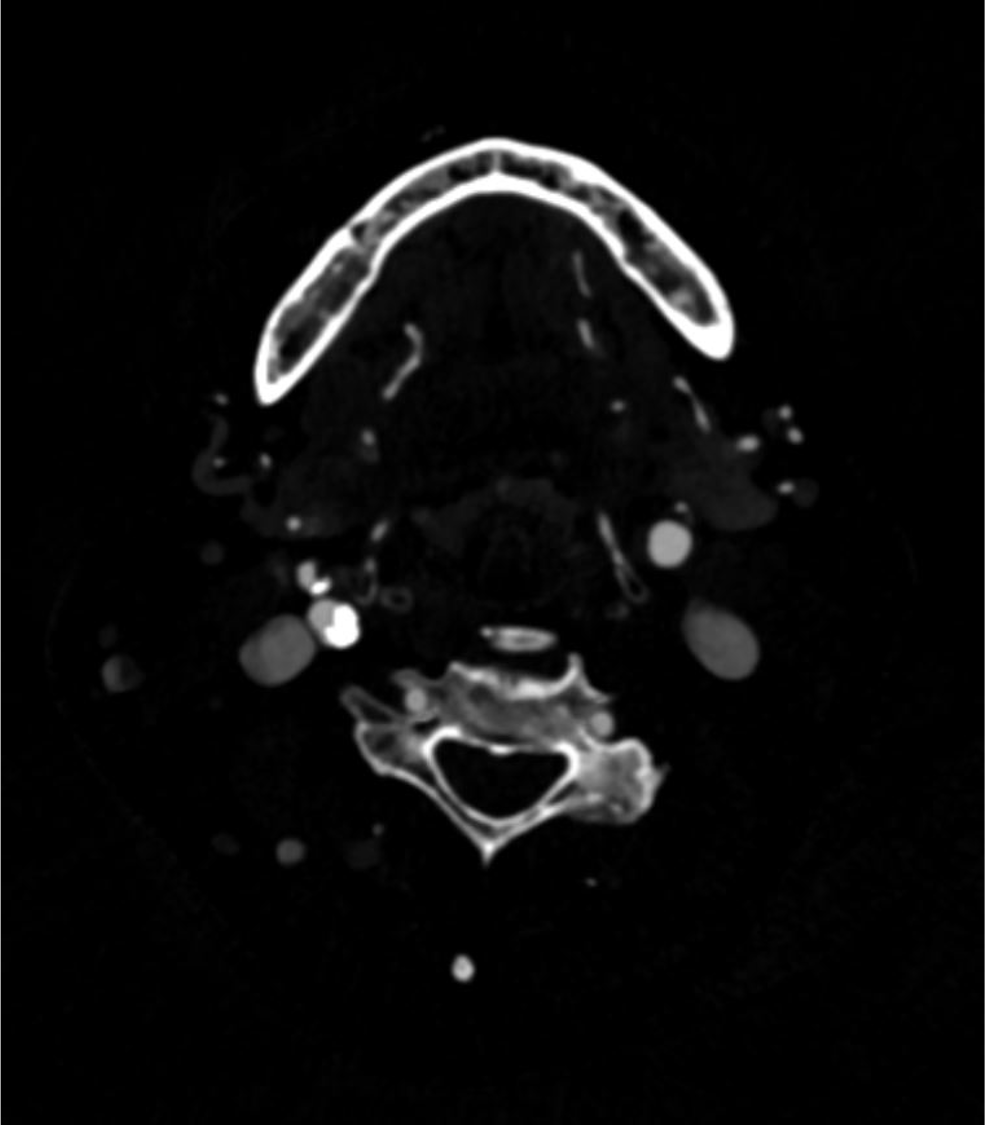

70歳代、男性、52kg、内頸動脈狭窄

右内頸動脈狭窄症の術前評価

2年前に左内頸動脈狭窄症に対して内膜剥離術施行後。今回、右内頸動脈狭窄の進行が疑われ、術前精査のためCT angiography施行。

内頸動脈狭窄症において、造影CTはMRIと並んで必須の検査である。MRIが苦手とする石灰化の評価、薄いスライス厚での狭窄率評価が、造影CTでは行いやすい。動脈相での評価が望ましく、血管内と血管外の境界が可能な限りシャープである方が、狭窄率の評価が行いやすい。